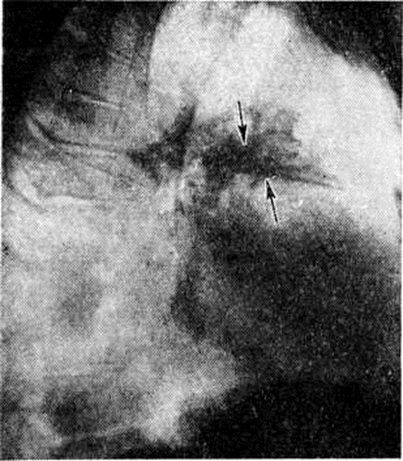

При перкуссии часто определяют признаки острого вздутия лёгких: тимпанит, низкое расположение краёв лёгких, уменьшение абсолютной сердечной тупости. Определяют небольшое укорочение перкуторного звука соответственно зоне инфильтрации и расширение корня лёгкого на поражённой стороне. При аускультации дыхание жёсткое, выслушиваются нестойкие скудные сухие хрипы, иногда сухих и влажных хрипов много. В некоторых случаях перкуторные и аускультативные признаки выражены слабо или отсутствуют. Часто между клинические, и рентгенологическое признаками гриппозных Пневмония наблюдается расхождение. Так, при выраженных рентгенологическое признаках пневмонической инфильтрации отсутствуют её физикальные проявления или, напротив, у больных с клинически выраженными признаками Пневмония рентгеноскопически и рентгенографически определяют лишь небольшое расширение прикорневых теней и отставание экскурсий диафрагмы. По данным Н. С. Молчанова (1971), чаще других поражаются задние сегменты верхних долей, верхушечный и задний базальный сегменты нижних долей. В начале заболевания выражена тахикардия, АД несколько повышается в первые дни болезни, а затем снижается.

При бруцеллезной Пневмония отмечается кашель с мокротой, кровохарканье, боли в грудной клетке, осиплость голоса. Рентгенологически выявляются инфильтративные изменения, локализующиеся в прикорневой зоне лёгкого или перибронхиально. Пневмония сопровождается лейкоцитозом, в мокроте обнаруживают возбудителей бруцеллёза.